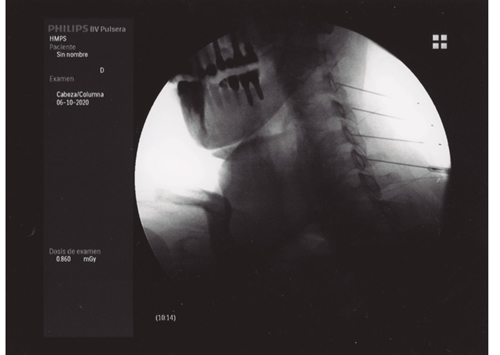

La neurotomía por radiofrecuencia del ramo medial es una técnica que está bien estandarizada a nivel cervical y lumbar, no así a nivel torácico, y que es un tratamiento que está bien establecido y estudiado con un nivel de evidencia alto (2,3,4). Por tanto, tras llegar al diagnóstico de dolor facetario el tratamiento de elección es la neurotomía por radiofrecuencia del ramo medial (Figuras 1 y 2).

Fig. 1.

Fig. 2.

La neurotomía por radiofrecuencia del ramo medial es una técnica estandarizada a nivel cervical y lumbar, con unos niveles de evidencia elevados y, por tanto, totalmente recomendable en el tratamiento del dolor facetario secundaria a la artrosis vertebral.